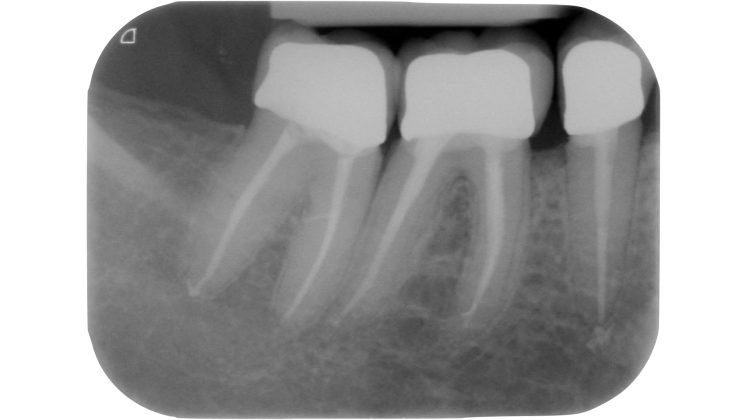

Una cavità d’accesso inadeguata per posizione, profondità ed estensione può determinare serie difficoltà nelle fasi successive, rendendo ad esempio difficile la localizzazione degli orifizi canalari, sottoponendo a eccessivo stress gli strumenti meccanici utilizzati o determinando un indebolimento della struttura dentale residua (Figure 1-5).

Devono essere valutate con molta attenzione la posizione dell’elemento in arcata e la sua inclinazione (Figure 6-7), l’entità e la posizione del processo carioso se presente, gli eventuali restauri posizionati sul dente e i rapporti con il parodonto: tutte queste considerazioni permetteranno al clinico di capire innanzitutto la mantenibilità e la possibilità di isolare mediante diga di gomma il dente. L’interpretazione degli esami radiografici consentirà inoltre di valutare alcuni parametri preoperatori di notevole importanza:

- presenza di pregresse terapie canalari e valutazione della qualità delle stesse;